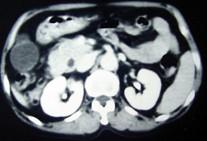

问题 男,55岁,中上腹隐痛多年,剑突下压痛,影像检查如图,最可能的诊断是 ( )

选项 A、十二指肠重复畸形 B、十二指肠穿孔 C、十二指肠憩室 D、十二指肠癌 E、十二肠溃疡

答案 C